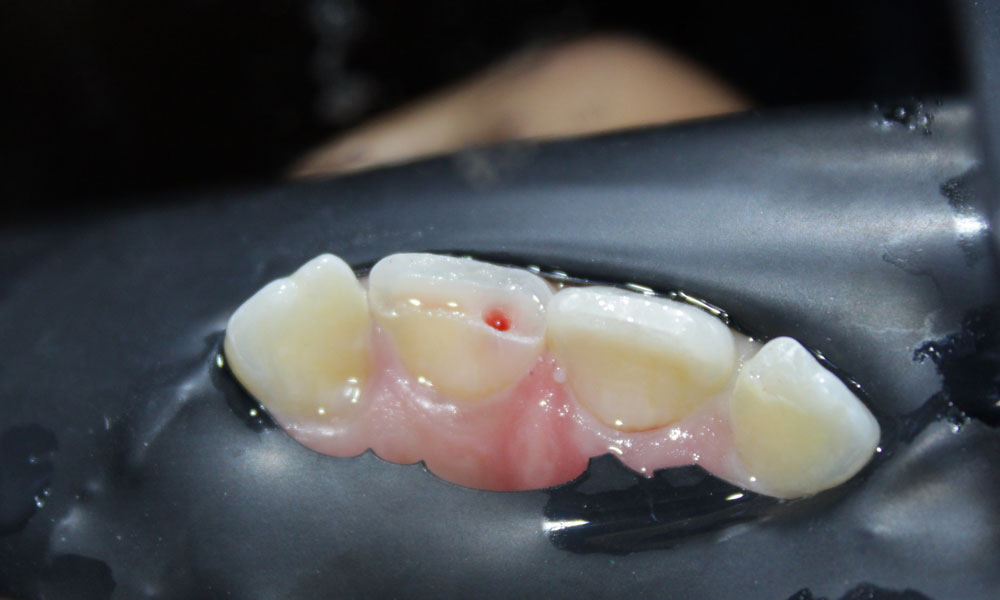

Pulpectomy/ Pulpotomy

Pulpectomy and pulpotomy are dental procedures designed to address issues with the pulp of a tooth. These procedures are commonly performed on primary and permanent teeth to treat decay or trauma affecting the tooth's inner structures.